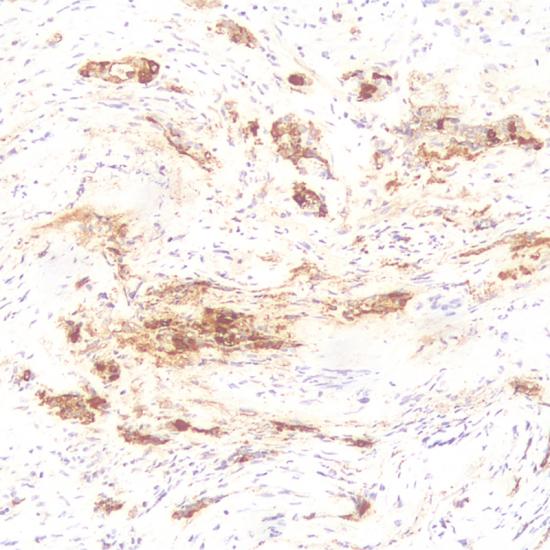

Luteinizing Hormone 抗體試劑(免疫組織化學(xué)) 閩廈械備20180132號(hào)

促黃體生成素是垂體細(xì)胞分泌的一種激素。此抗體和人的促黃體生成素反應(yīng),和促甲狀腺素、卵泡刺激素、絨毛膜促性腺激素有微弱交叉反應(yīng),主要用于垂體腺瘤功能性分類的研究。